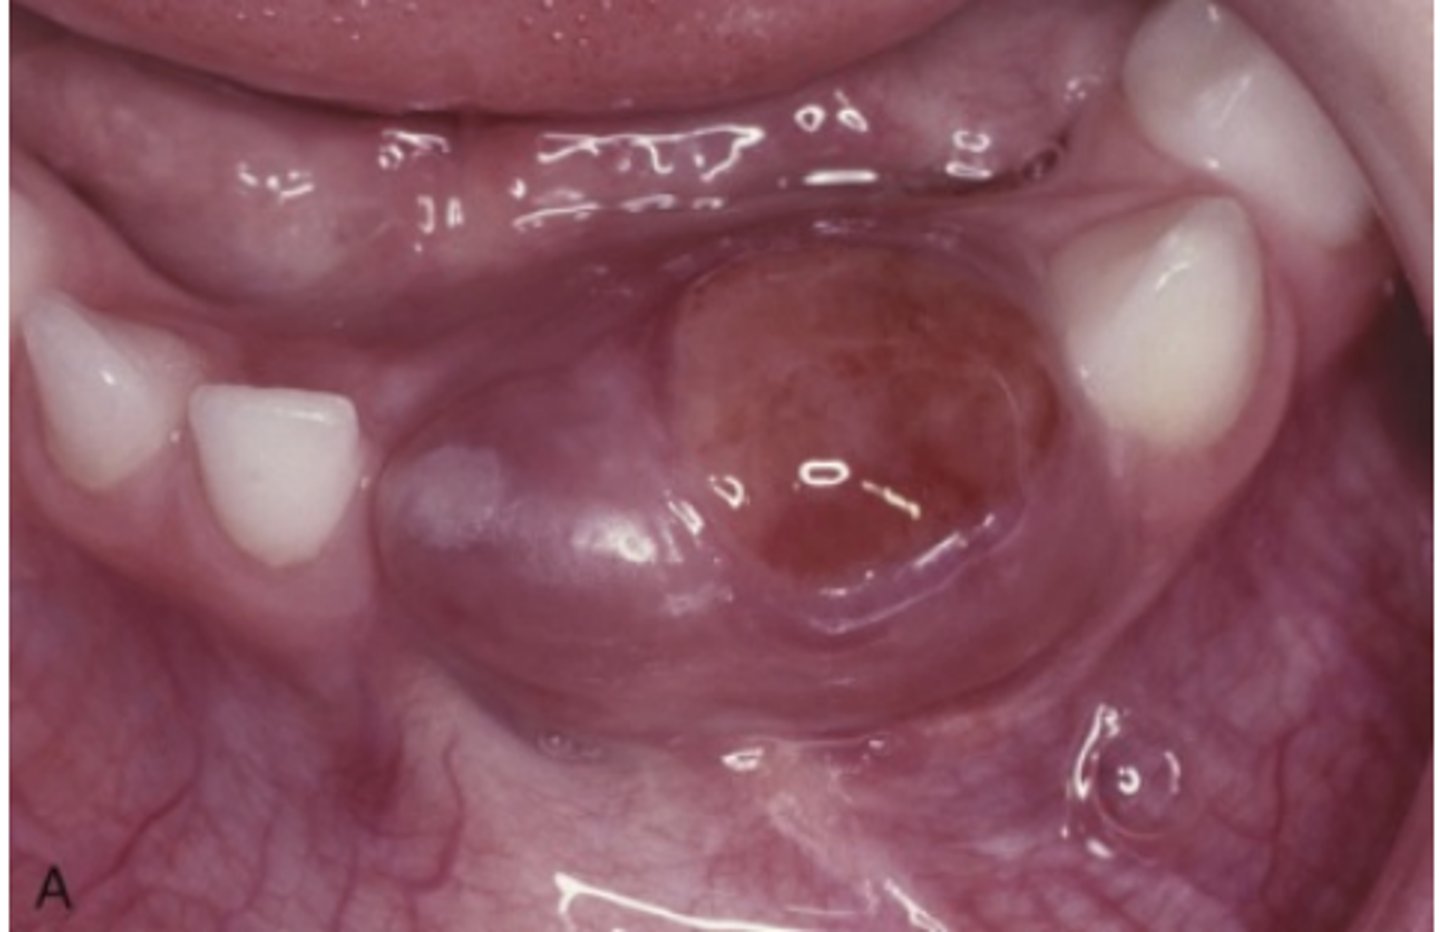

What type of lesion is a Central Giant Cell Granuloma?

An intraosseous lesion.

What is the main controversy surrounding the nature of Central Giant Cell Granuloma?

Whether it is a reactive process or a benign neoplasm.

Where is the most frequent location of Central Giant Cell Granuloma?

70% occur in the mandible

What area of the mouth is Central Giant Cell Granuloma more common?

More common in anterior portion of jaws

What are the two categories of Central Giant Cell Granuloma based on clinical and radiographic features?

Nonaggressive lesions and Aggressive lesions.

What are typical characteristics of nonaggressive Central Giant Cell Granulomas?

Relatively small, few or no symptoms, slow growth, no cortical perforation or root resorption, usually discovered during routine radiographs or due to painless jaw expansion.

How do aggressive Central Giant Cell Granulomas typically present?

Pain, rapid growth, cortical perforation, root resorption, tooth displacement, paresthesia, soft tissue extension, and mucosal ulceration.

What is the treatment for Central Giant Cell Granuloma

Thorough curettage